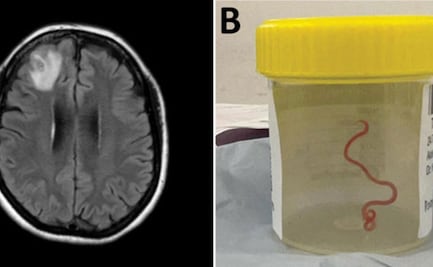

Médicos hallan lombriz intestinal de 8 cm en el cerebro de una mujer: "estaba vivo y retorciéndose"

La mujer, de 64 años, fue internada en enero de 2021 en un hospital de Camberra tras padecer durante tres semanas de dolor abdominal y diarrea, seguidos de fiebre, tos, sudores nocturnos y dificultad para respirar